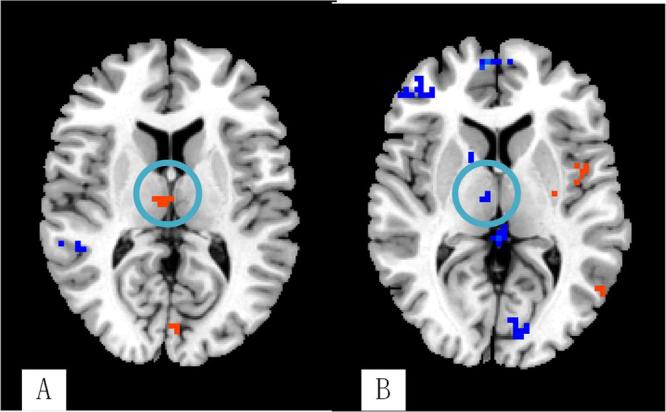

Research on the mechanism of post stroke depression (PSD) is the key way to improve the treatment of PSD. However, the functional brain network of PSD has not been entirely supported by the results of functional magnetic resonance imaging (fMRI) studies. The aims of this study are to investigate the brain response of PSD in three different lesions. The brain responses of the three PSD subgroups were similar. However, each subgroup had its own characteristics of the brain network. In the temporal lobe subgroup, the right thalamus had increased degree centrality (DC) values which were different from the other two subgroups. In the frontal lobe subgroup, the left dorsolateral prefrontal cortex, caudate, and postcentral gyrus had increased DC values which were different from the other two subgroups. The hemodynamic response of PSD indicates that PSD has activities of similar emotional networks, of which the negative network realizes its function through the limbic system and default mode network. The brain network has unique characteristics for different lesion locations. The neurological function of the lesion location, the compensatory mechanism of the brain, and the mechanism of integrity and locality of the brain are the important factors in the individual emotional network.

研究脑卒中后抑郁(PSD)的发病机制是提高 PSD 治疗效果的关键途径。然而,功能磁共振成像(fMRI)研究结果并未完全支持 PSD 的功能脑网络。本研究旨在探讨三种不同病变部位 PSD 的脑反应。三组 PSD 亚组的脑反应相似,但每个亚组的脑网络都有其自身的特点。在颞叶亚组中,右侧丘脑的度中心度(DC)值增加,与其他两组不同。在额叶亚组中,左侧背外侧前额叶皮层、尾状核和中央后回的 DC 值增加,与其他两组不同。PSD 的血液动力学反应表明 PSD 具有相似的情绪网络活动,其中负性网络通过边缘系统和默认模式网络实现其功能。不同病变部位的脑网络具有独特的特征。病变部位的神经功能、大脑的代偿机制以及大脑的完整性和局部性机制是个体情绪网络的重要因素。